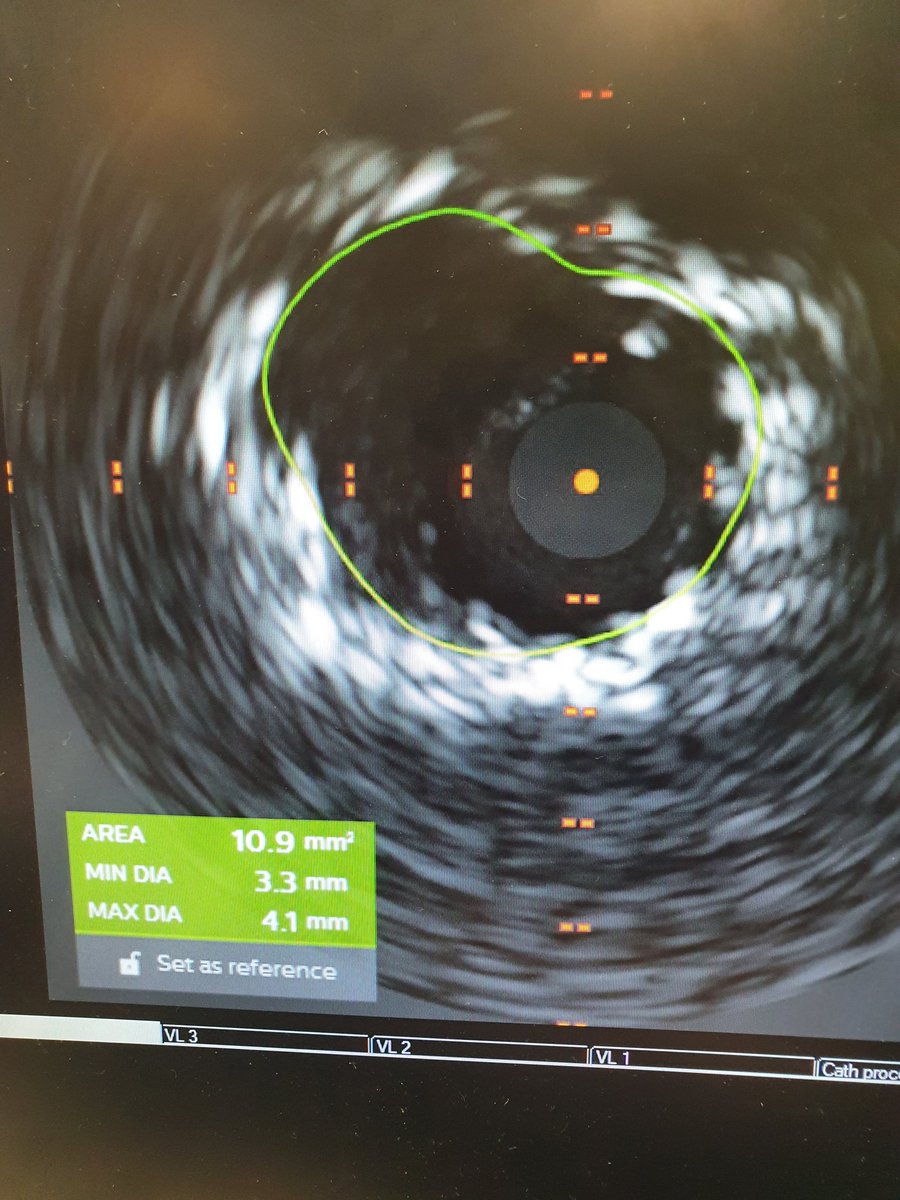

Interventional cardiologist, Lancashire Cardiac Centre, UK. Past fellow Uni of Western Ontario, Canada. Cardiology Manchester.BartsSMD.